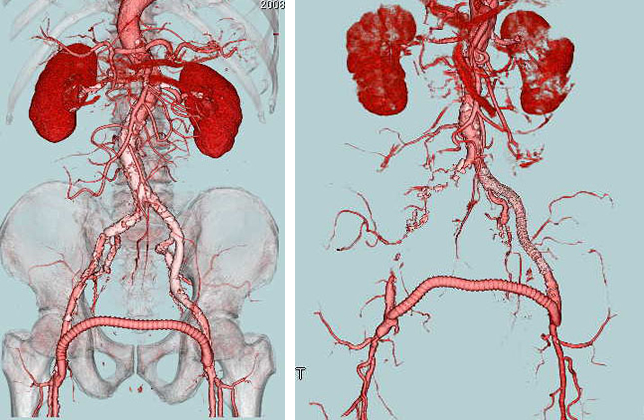

- 大動脈狭窄 【写真】

- 高位大動脈閉塞(Leriche synd) 【写真】

- 腸骨動脈完全閉塞(右) 【写真】

- 腸骨動脈狭窄 【写真】

考え方としては、早期であるほど2の血管内手術のみで治る可能性が高いと考えてよいでしょう。現在の末梢動脈に対する血管内手術の適応は、大動脈・腸骨動脈領域から膝下動脈、さらに足関節から足趾にまで及びます。しかし、それぞれの治療法には当然ながら適応があります。このためしばしば従来からの手術との組み合わせであるハイブリッド手術が必要になりますが、血管内呪術の関与する割合は8~9割にも及んでいます。